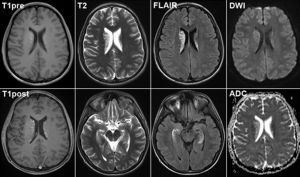

• рентгенологічне дослідження черепа — виявляє відсутність швів (одного або декількох ), витончення кісткової структури, МРТ черепа наявність пальцевих вдавлений на черепних кістках, деформацію черепа;

• КТ (комп'ютерна томографія) або МРТ (магнітно-резонансна томографія ) — метод нейровізуалізації, крім змін кісткової структури дозволяє визначити ступінь вираженості внутрішньочерепноїгіпертензії;